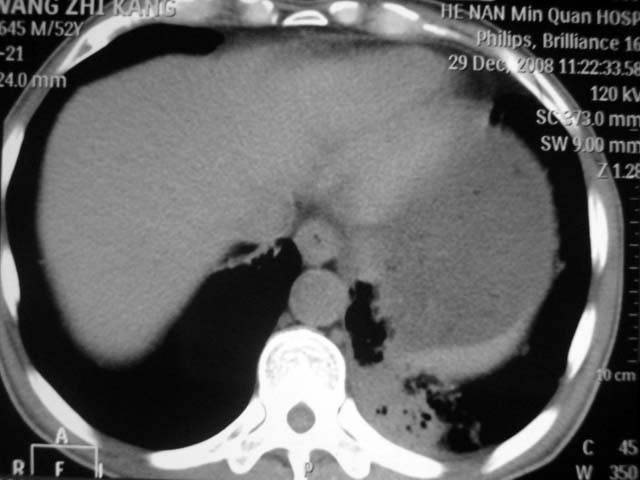

男,52岁,发热2月,糖尿病史。

抗结核治疗irpz方案,血糖未治疗,空腹15.9左右。症状无好转,左胸痛。

复查ct

2、双肺见多发片状及结节状高密度影,大多数病灶中心均见“空泡征”。

3、纵隔内淋巴结肿大。

结果:两肺继发性肺结核并曲霉菌感染。